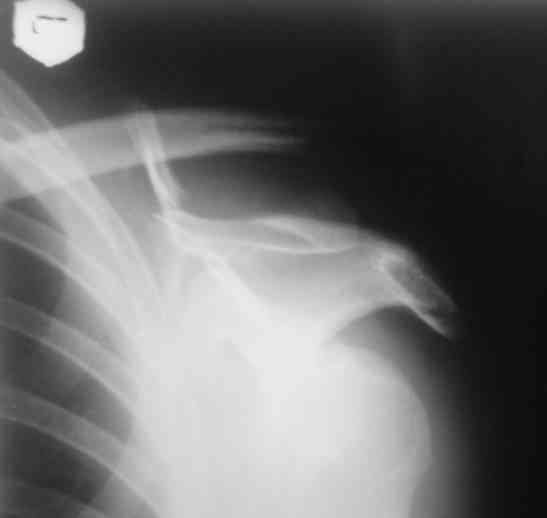

Для решения насчет оперативного вмещательства на лопатке сперва надо определиться с обьязательными ренгенологическими исследованиями, не менее трех стандартных проекций: прямая, аксиллярная и в позиции виде “Y”.

Прямую снимают под углом в 35 градусов от центра и вид “Y” в 90 градусов к нему. Несмотря на неудобства, больному необходимо сделать

аксиллярный снимок.

К-томографические и Трехмерные(3D)снимки крайне важны для определения внутрисуставных переломов и классификации.

Кроме анатомической классификации, переломы лопатки делятся на стабильные и нестабильные, внутри- и внесуставные и с вовлечением суставной поверхности.

Нестабильные внесуставные переломы лопатки типично сочетаются с переломами ключицы и ребер.

Посмотрел пациента под рентгеноскопом, определяется изолированный перелом верхнего медиального угла лопатки. Вопрос об операции отпал. Больной машет крылом как пропеллером, пришлось ограничить активность дисциплинирующей "косынкой" ... :))) Отек мягких тканей в области